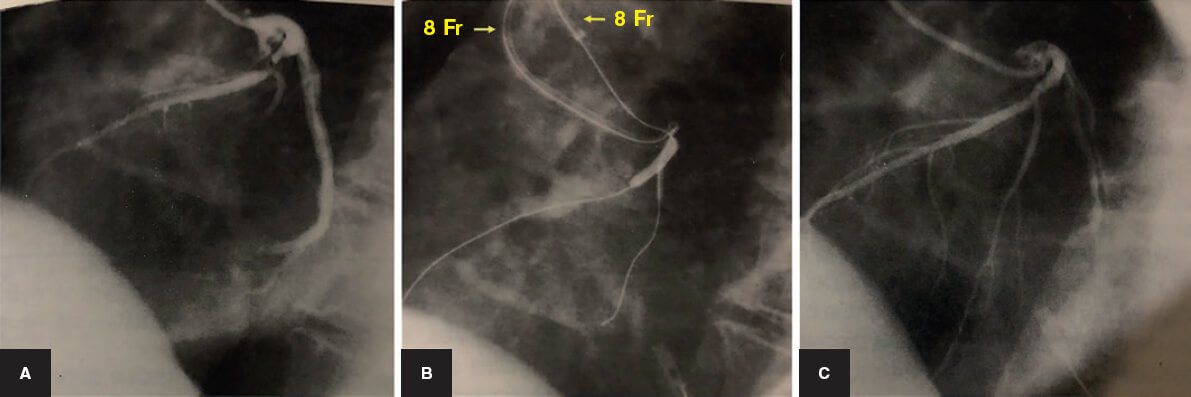

El tratamiento percutáneo de las bifurcaciones comienza en la era de la angioplastia con balón, previamente a la disponibilidad del stent coronario. Por aquel entonces ya se describían técnicas específicas, como el uso de 2 catéteres guía de 8 Fr por los que se introducían guías y balones de forma independiente en el vaso principal (VP) y en la rama lateral (RL) para realizar un inflado simultáneo (figura 1). Sin embargo, el punto de inflexión del tratamiento percutáneo de las bifurcaciones lo marcó la llegada del stent de Palmaz-Schatz. La primera técnica que se describió fue una dilatación simple con balón de la RL a través de las celdillas del stent4. A partir de entonces se describió un sinfín de técnicas para tratar ambos vasos con 1 o 2 stents. Con la llegada de los stents farmacoactivos se mejoraron los resultados de todos los procedimientos coronarios. En el campo de las bifurcaciones, se adoptó la experiencia adquirida en la época de los stents metálicos y se desarrollaron también algunas nuevas técnicas complejas: el crush y sus variantes, el TAP (T y protrusión) y el simultaneous kissing stents (SKS).

Figura 1. Bifurcación en la arteria descendente anterior/rama diagonal. Tratamiento percutáneo en la era anterior a los stents. A: angiografía basal. B: dilatación con balón de la descendente anterior y diagonal. Dos catéteres guía femorales de 8 Fr con guías y balones independientes para realizar una dilatación simultánea de los balones (kissing balloon). C: resultado final.